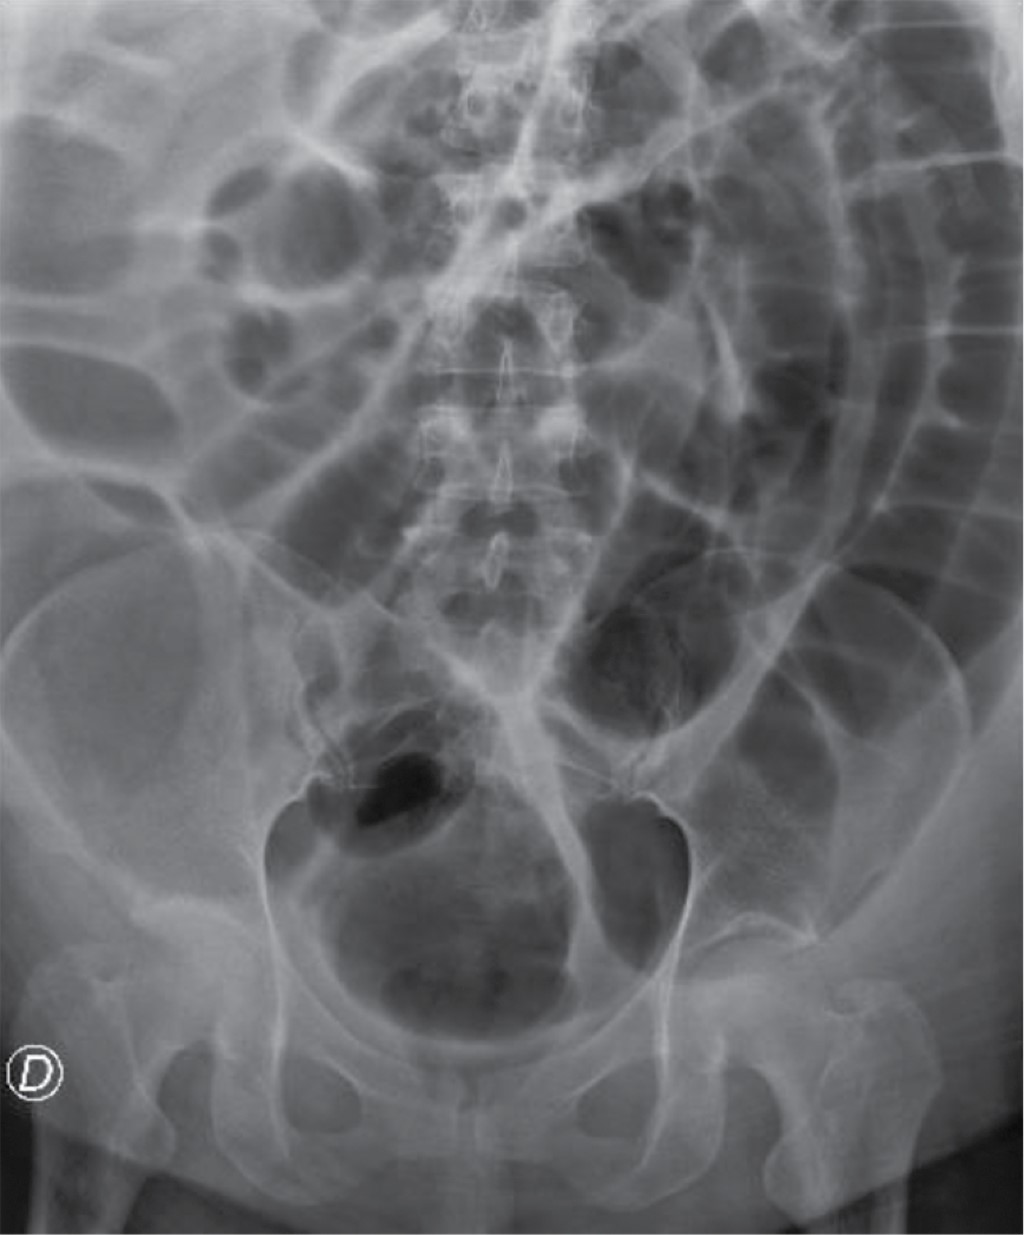

Mujer de 39 años con antecedente de diabetes mellitus tipo 2, hipertensión e hipotiroidismo, acudió a urgencias con quemaduras superficiales y profundas (segundo y tercer grado) en la cara (Figura 1), brazo derecho y extremidades inferiores circunferenciales (Figuras 2 y 3). Se realizó fibronasoendoscopia por otorrinolaringología y se descartó quemadura de la vía aérea. Se calculó la superficie corporal total quemada en 24%, se administró líquidos con la fórmula de Parkland con solución Hartmann 950 mL/h durante las primeras ocho horas, con diuresis a 0.5 mL/kg/h. La paciente fue ingresada en el piso de cirugía plástica para seguimiento. Al segundo día se quejó de dolor y distensión abdominal, por lo que se tomaron radiografías de abdomen (Figura 4) que revelaron distensión intestinal. Se decidió realizar tomografía computarizada que mostraba distensión de hasta 8.5 cm en colon (Figura 5), sin evidencia de obstrucción mecánica. Los electrolitos séricos eran normales. Se decidió dar manejo conservador en piso por 72 horas, con mejoría clínica. Se retiró la sonda nasogástrica y toleró la dieta. Se vigiló por 48 horas y se decidió su egreso por mejoría clínica. Acudió a consulta 10 meses después, negando cuadros de dolor abdominal y tolerando la vía oral. Se encontraba en rehabilitación por las quemaduras.

Como cirujanos plásticos y reconstructivos es importante conocer las causas relacionadas con la pseudoobstrucción de colon aguda para sospechar de esta entidad, ya que el reconocimiento temprano y buen manejo de esta patología reducirá la morbimortalidad de nuestros pacientes. El manejo conservador es el de elección en el síndrome de Ogilvie. El estudio de imagen ideal es la tomografía contrastada de abdomen para valorar un posible sitio de oclusión o complicación. En nuestro caso, la paciente tuvo un buen resultado con el manejo conservador. Es importante conocer esta etiología y reportarla en pacientes quemados.

Figura 4